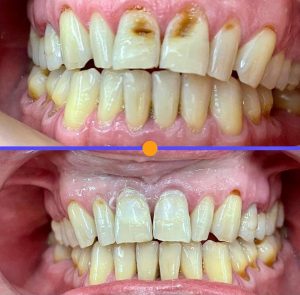

Tratamientos Ortodoncia Blanqueamiento dental Zoom Contacto 72 2795 9597 Marcar Ahora Envia whatsapp Visita nuestro facebook